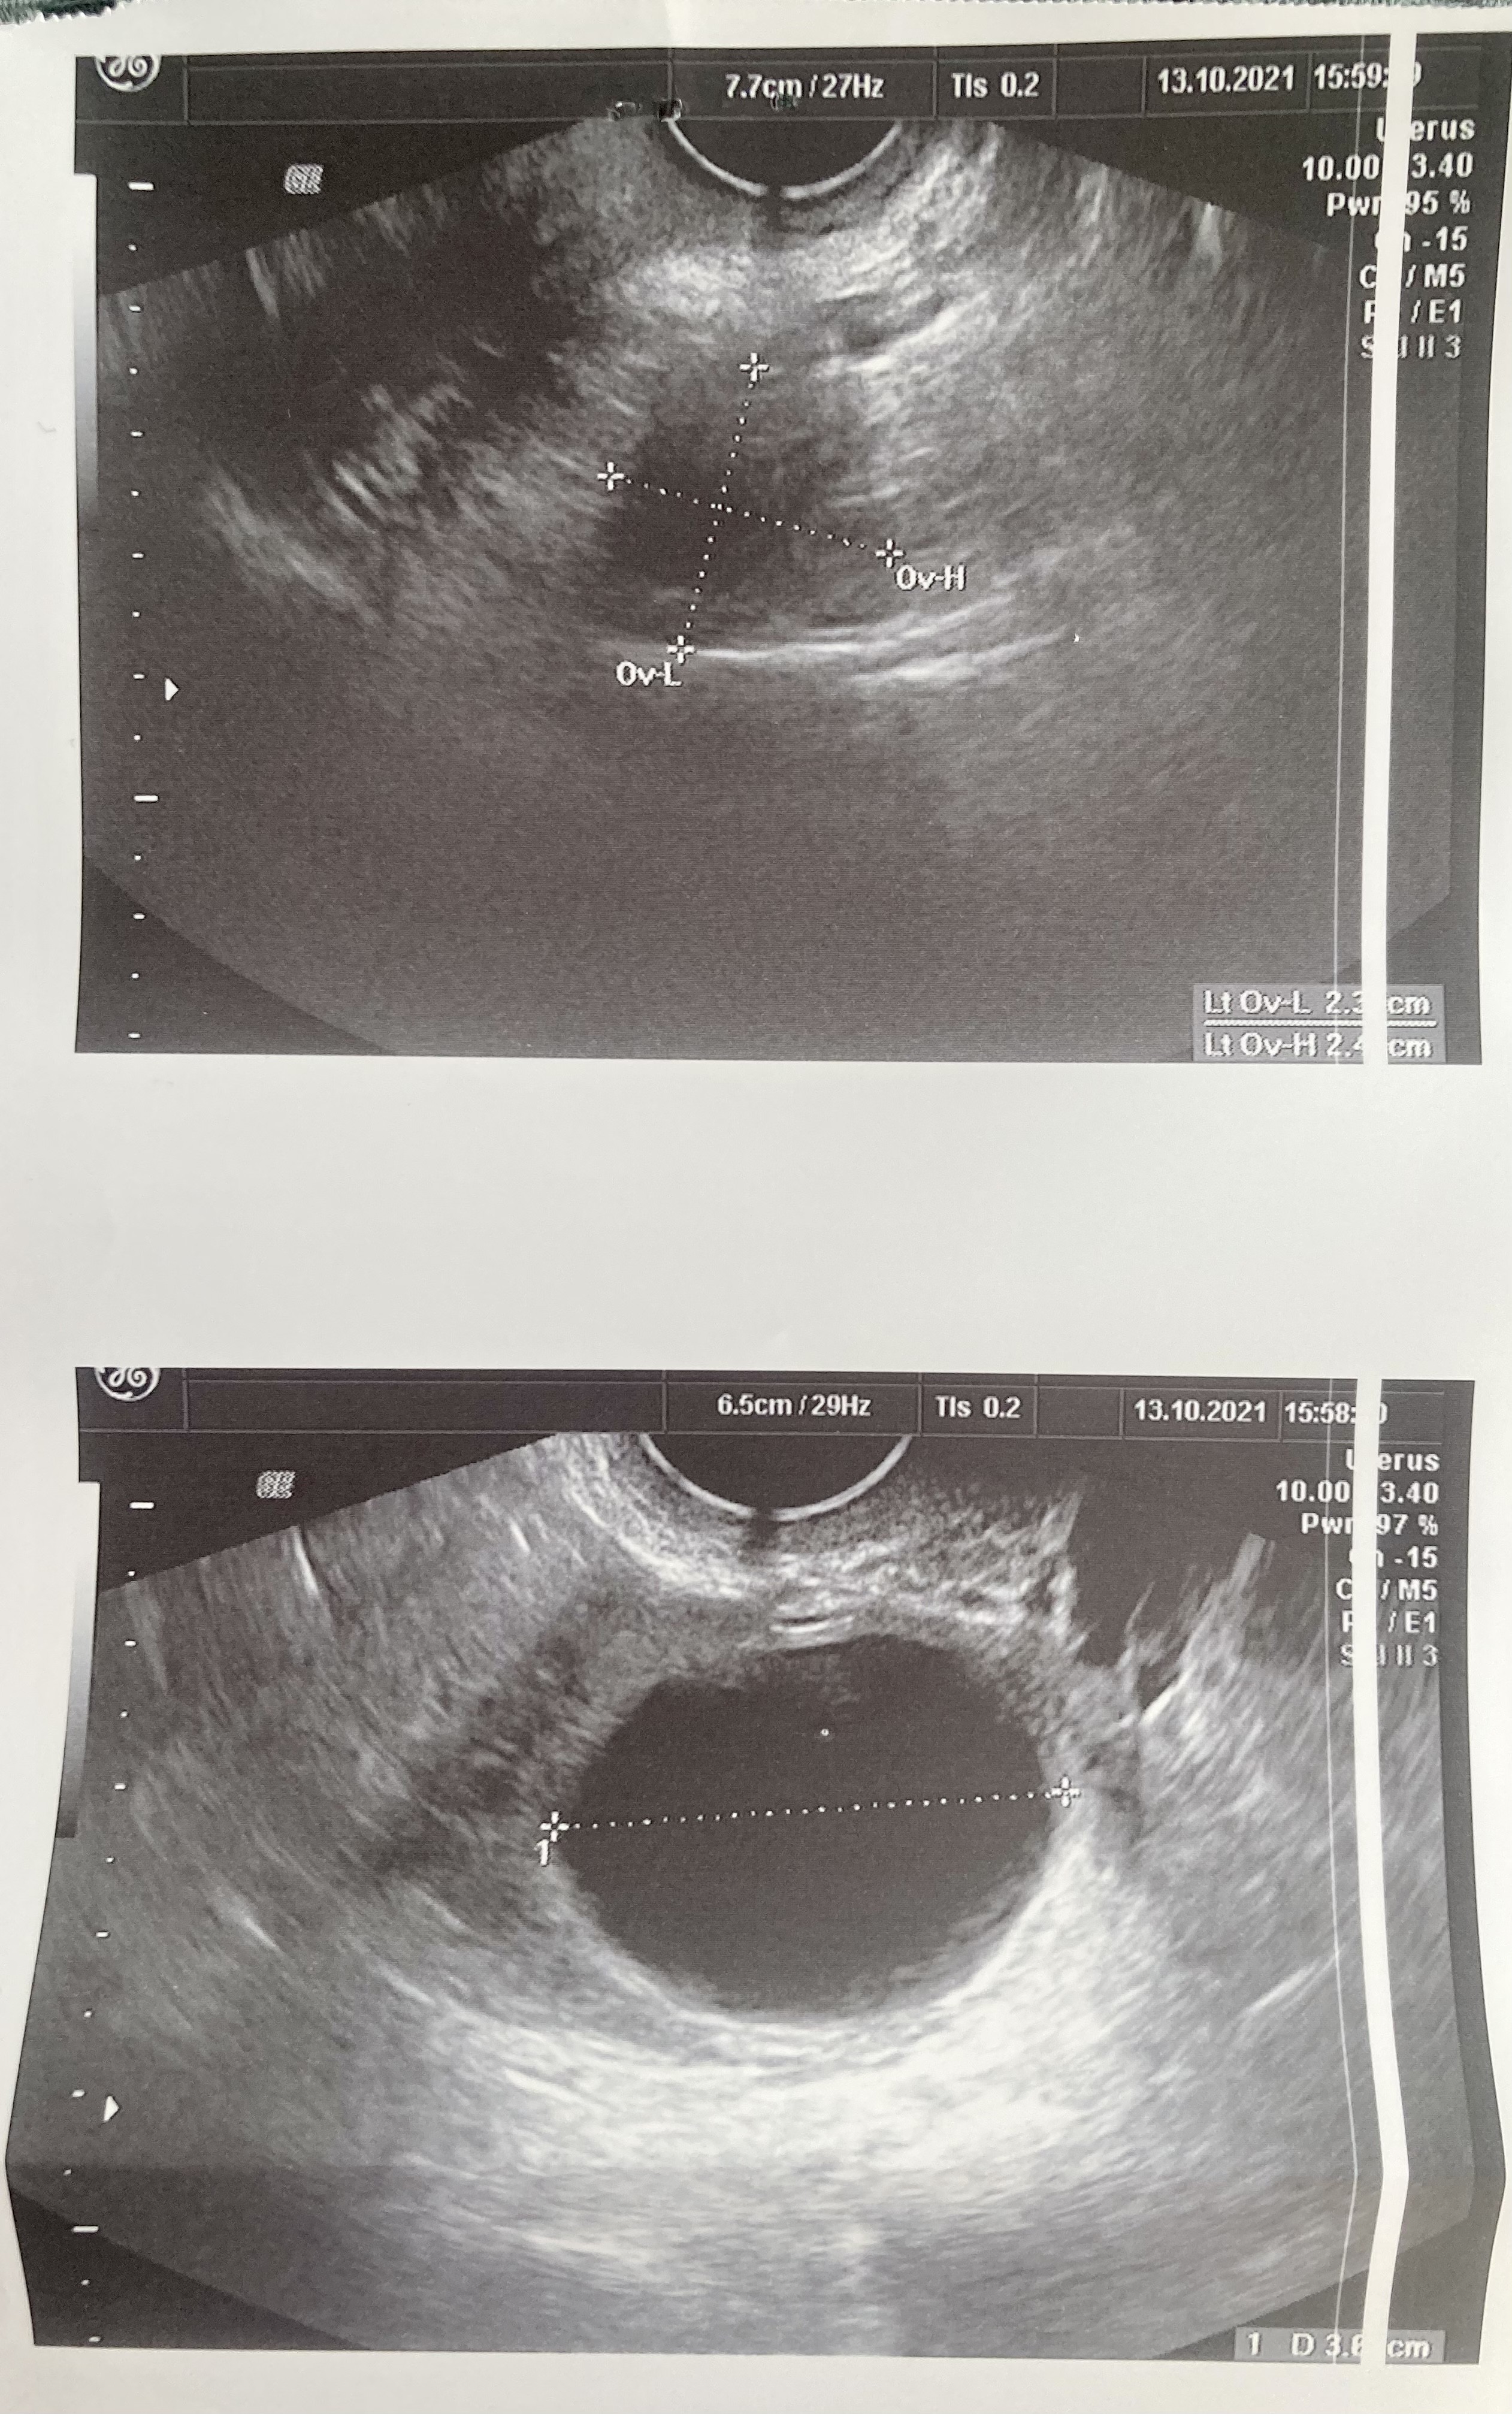

Co więcej, właśnie wyciągnęłam zapis usg i wychodzi, ze ta torbiel ma 6,5cm a nie 3,5 🙈 nie za bardzo ogarniam obraz na usg, ale jak w mordę strzelił jest 6,5cm.

• F3411FB7-F7D6-444A-8127-AECC3D6B5334.jpeg

F3411FB7-F7D6-444A-8127-AECC3D6B5334.jpeg

2 MB · Wyświetleń: 88

• 90716A2F-7AC1-4AE4-927A-0776D9432447.jpeg

90716A2F-7AC1-4AE4-927A-0776D9432447.jpeg

2 MB · Wyświetleń: 89

• 33DED63C-B319-4B06-8ED9-AB1C7413B1AC.jpeg

33DED63C-B319-4B06-8ED9-AB1C7413B1AC.jpeg

1,2 MB · Wyświetleń: 86